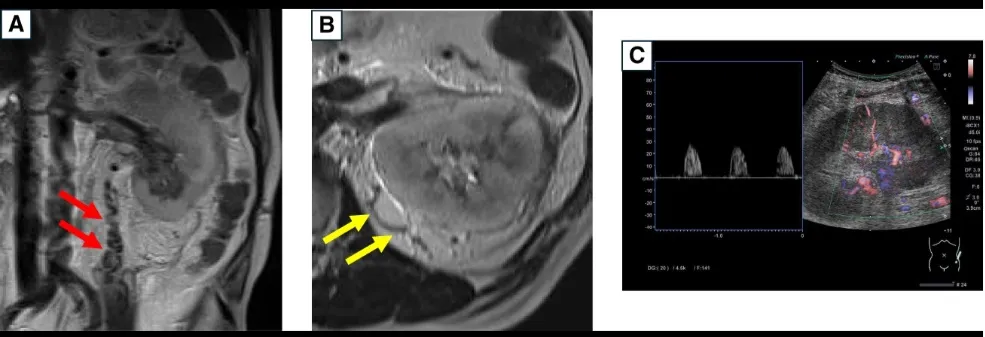

A ressonância magnética (abaixo) mostrou dilatação da veia testicular esquerda e da veia capsular renal. A tomografia computadorizada sem contraste revelou rim esquerdo aumentado, veia renal esquerda dilatada e infiltração perirrenal. Ultrassonografia Doppler mostrou fluxo sistólico isolado nas artérias interlobares, sugerindo congestão renal. Foi confirmado trombose da veia renal com êmbolo na junção com a veia testicular.

Achados de ressonância magnética sem contraste e ultrassonografia Doppler que sugerem trombose da veia renal. (A e B) Ressonância magnética mostrando aumento da (A) veia testicular esquerda e da (B) veia capsular renal. (C) Ultrassonografia Doppler da artéria interlobar mostrando fluxo sanguíneo apenas na fase sistólica.